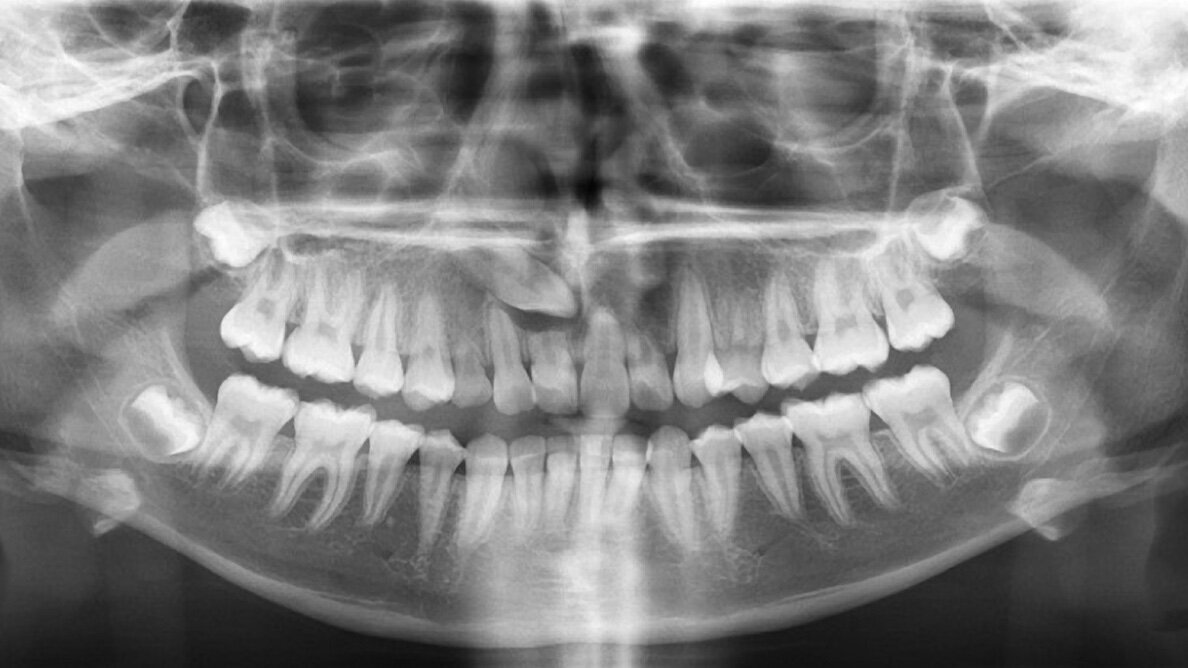

Fig. 1. Radiografía panorámica que muestra la ubicación del canino superior derecho retenido y alterando las estructuras óseas y dentarias.

Paciente de 16 años presenta un canino superior retenido con una formación quística que ha reabsorbido las raíces de las a piezas 11, 12 y 53 (Fig. 1).